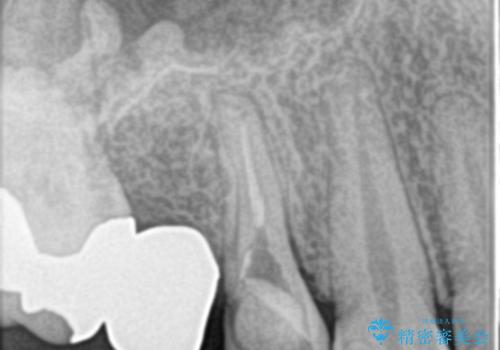

右上のブリッジが途中で切断されて、手前の歯が根の治療の途中でした。

根の治療を行いその後にオールセラミックブリッジを装着する計画となりました。